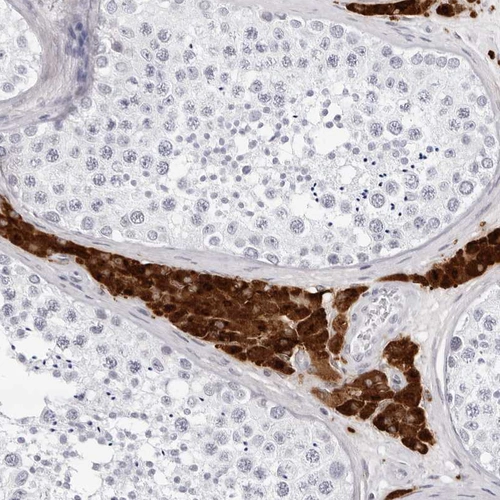

Immunohistochemistry analysis in human testis and liver tissues using HPA028615 antibody. Corresponding INSL3 RNA-seq data are presented for the same tissues.